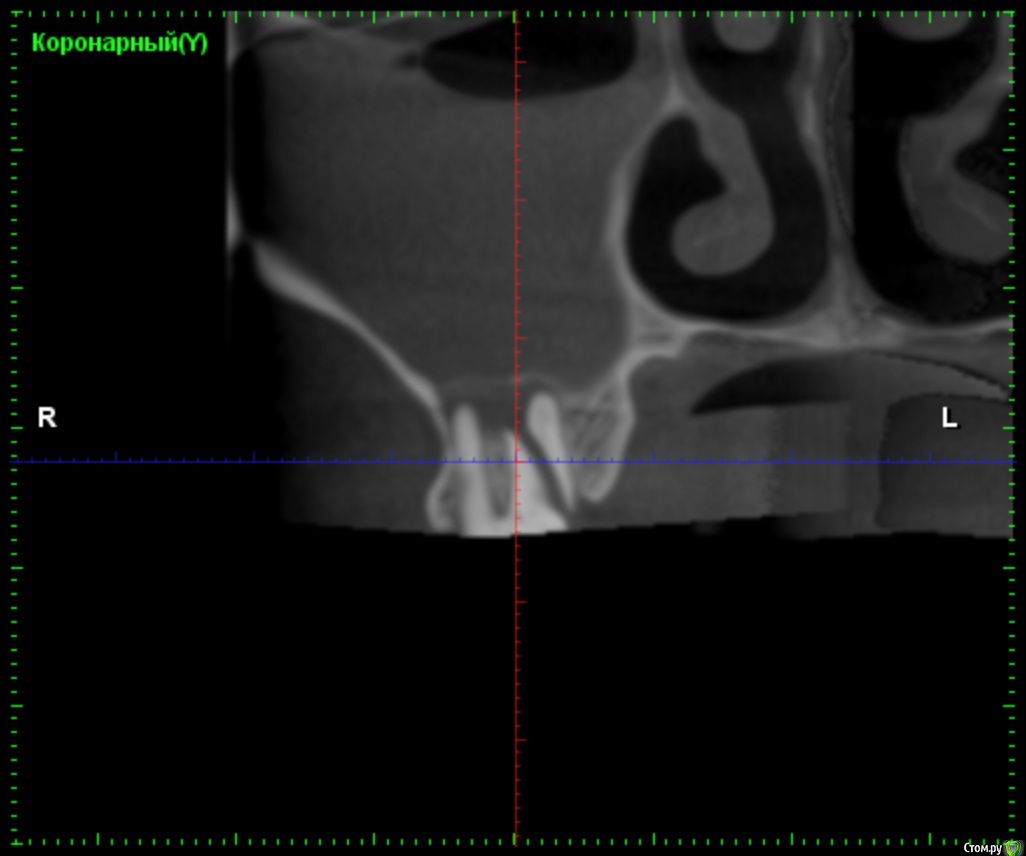

olersh Опубликовано 4 ноября, 2015 Поделиться Опубликовано 4 ноября, 2015 Здравствуйте, уважаемые доктора!20 октября 2015 г. начала лечить заболевший 17 зуб с диагнозом периодонтит. Из коренных он остался единственный - хожу с "мостом". Зуб решили сохранить и сразу начали лечение (снимки сделали после лечения, их приложить не могу, ибо не выдали). Ввели лекарство на две недели - следующий прием назначили на 3 ноября. Назначили найз через 12 часов, пока есть боль. Зуб болел достаточно сильно после лечения, но врач сказала терпеть или удалять. Решила терпеть. С 23 по 27 поднялась была температура в среднем 37,5 °С.29 октября вдруг через носоглотку стал выделяться гной с жутким запахом и первые несколько часов еще и ужасной горечью. Зуб сразу стал меньше болеть. Позвонила врачу, спросила - не может ли произойти прободение из полости зуба в пазуху. Врач сказала, что у меня гранулема, и, возможно, она разрушается под воздействием лекарства, успокоила, что ничего страшного, день приема не перенесла, про лекарства тоже ничего нового не сказала (продолжаю пить найз).31 октября, в субботу снова позвонила врачу (страшно мне из-за гноя). Попросила выписать хотя бы антибиотик. Выписали амоксиклав 1000. Предположили, что у меня обычный гайморит (раньше никогда не болела этой заразой), предложили обратиться к лору, чтобы выяснить, можно ли лечить зуб или надо его удалять.2 ноября сходила в челюстно-лицевую хирургию. Они подтвердили, что надо к лору, но сказали, что лучше сделать снимок КТ, на котором должна быть видна перфорация, если она есть. 3 ноября сделала КТ, с ним пришла на прием к стоматологу. В итоге КТ толком не посмотрели, но снова отправили к лору - пойду завтра.Уважаемые стоматологи, посмотрите, пожалуйста, снимки! Если необходимо, могу выложить в других ракурсах или даже сам файл прислать, если у вас есть такая программа. Ссылка на комментарий

red_butler Опубликовано 4 ноября, 2015 Поделиться Опубликовано 4 ноября, 2015 Спасибо! Если можно, приведите, пожалуйста, аргументы, хотя бы вкратце?перелом корня, это не лечится 2 Ссылка на комментарий